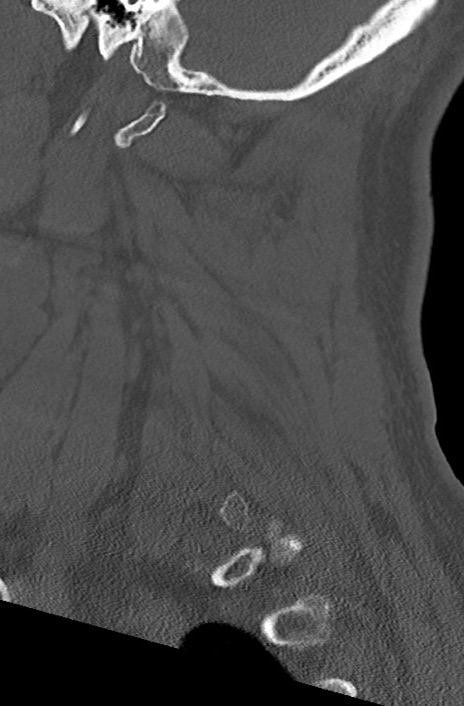

頚椎CT

矢状断像と横断像